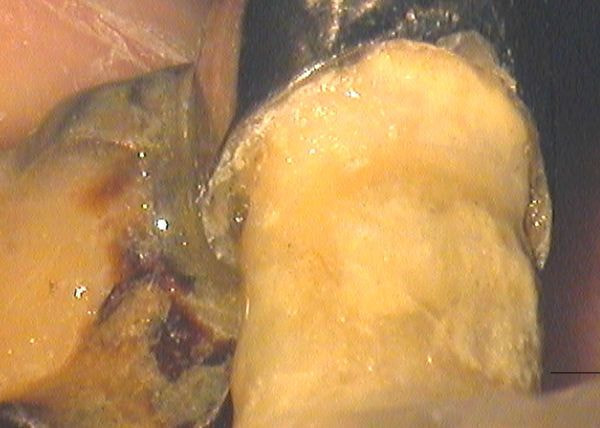

虫歯が発生するのは、歯と修復物の継ぎ目の部分であることがほとんどです。上の写真のブリッジは、ある重症の歯周病患者さんのお口の中にあった物です。かぶせ物の継ぎ目の部分に大きな虫歯が出来ているのがわかります。どちらも神経がない歯でしたので、痛むことがなく、そのままにしていたところ、歯周病が進行し、自然に抜けてしまいました。

image

上の写真はブリッジの継ぎ目の部分を下の方から見た写真ですが、歯とかぶせ物の間に大きなすき間があるのがおわかりいただけると思います。このようにお手入れしようにもできないような段差があったり、すき間があるような修復物はプラークの人工的な蓄積場となり、そこから将来むし歯が発生してくるのです。プラークコントロールは患者さんの責任ですが、修復物の品質は歯科医師の責任になります。このようなかぶせ物やつめ物がはいってしまうと、患者さんがどんなに頑張って予防しようとしても、限界が出来てしまいます。

上の写真の矢印は、歯の根にはいったクラック(ひび)を示しています。入れ歯を支えていた歯だったのですが、咬合時に違和感を訴えていました。顕微鏡で確認したところ破折線が認められましたので、相談の上抜歯させていただいたものです。私のところで治療させていただきましたが、残念ながら8年目に抜歯になりました。かぶせ物の継ぎ目に全く隙間がないことに注目してください。適合の良い修復物は虫歯になりにくいのですが、このように力によってだめになる場合もあることを知っておいてください。